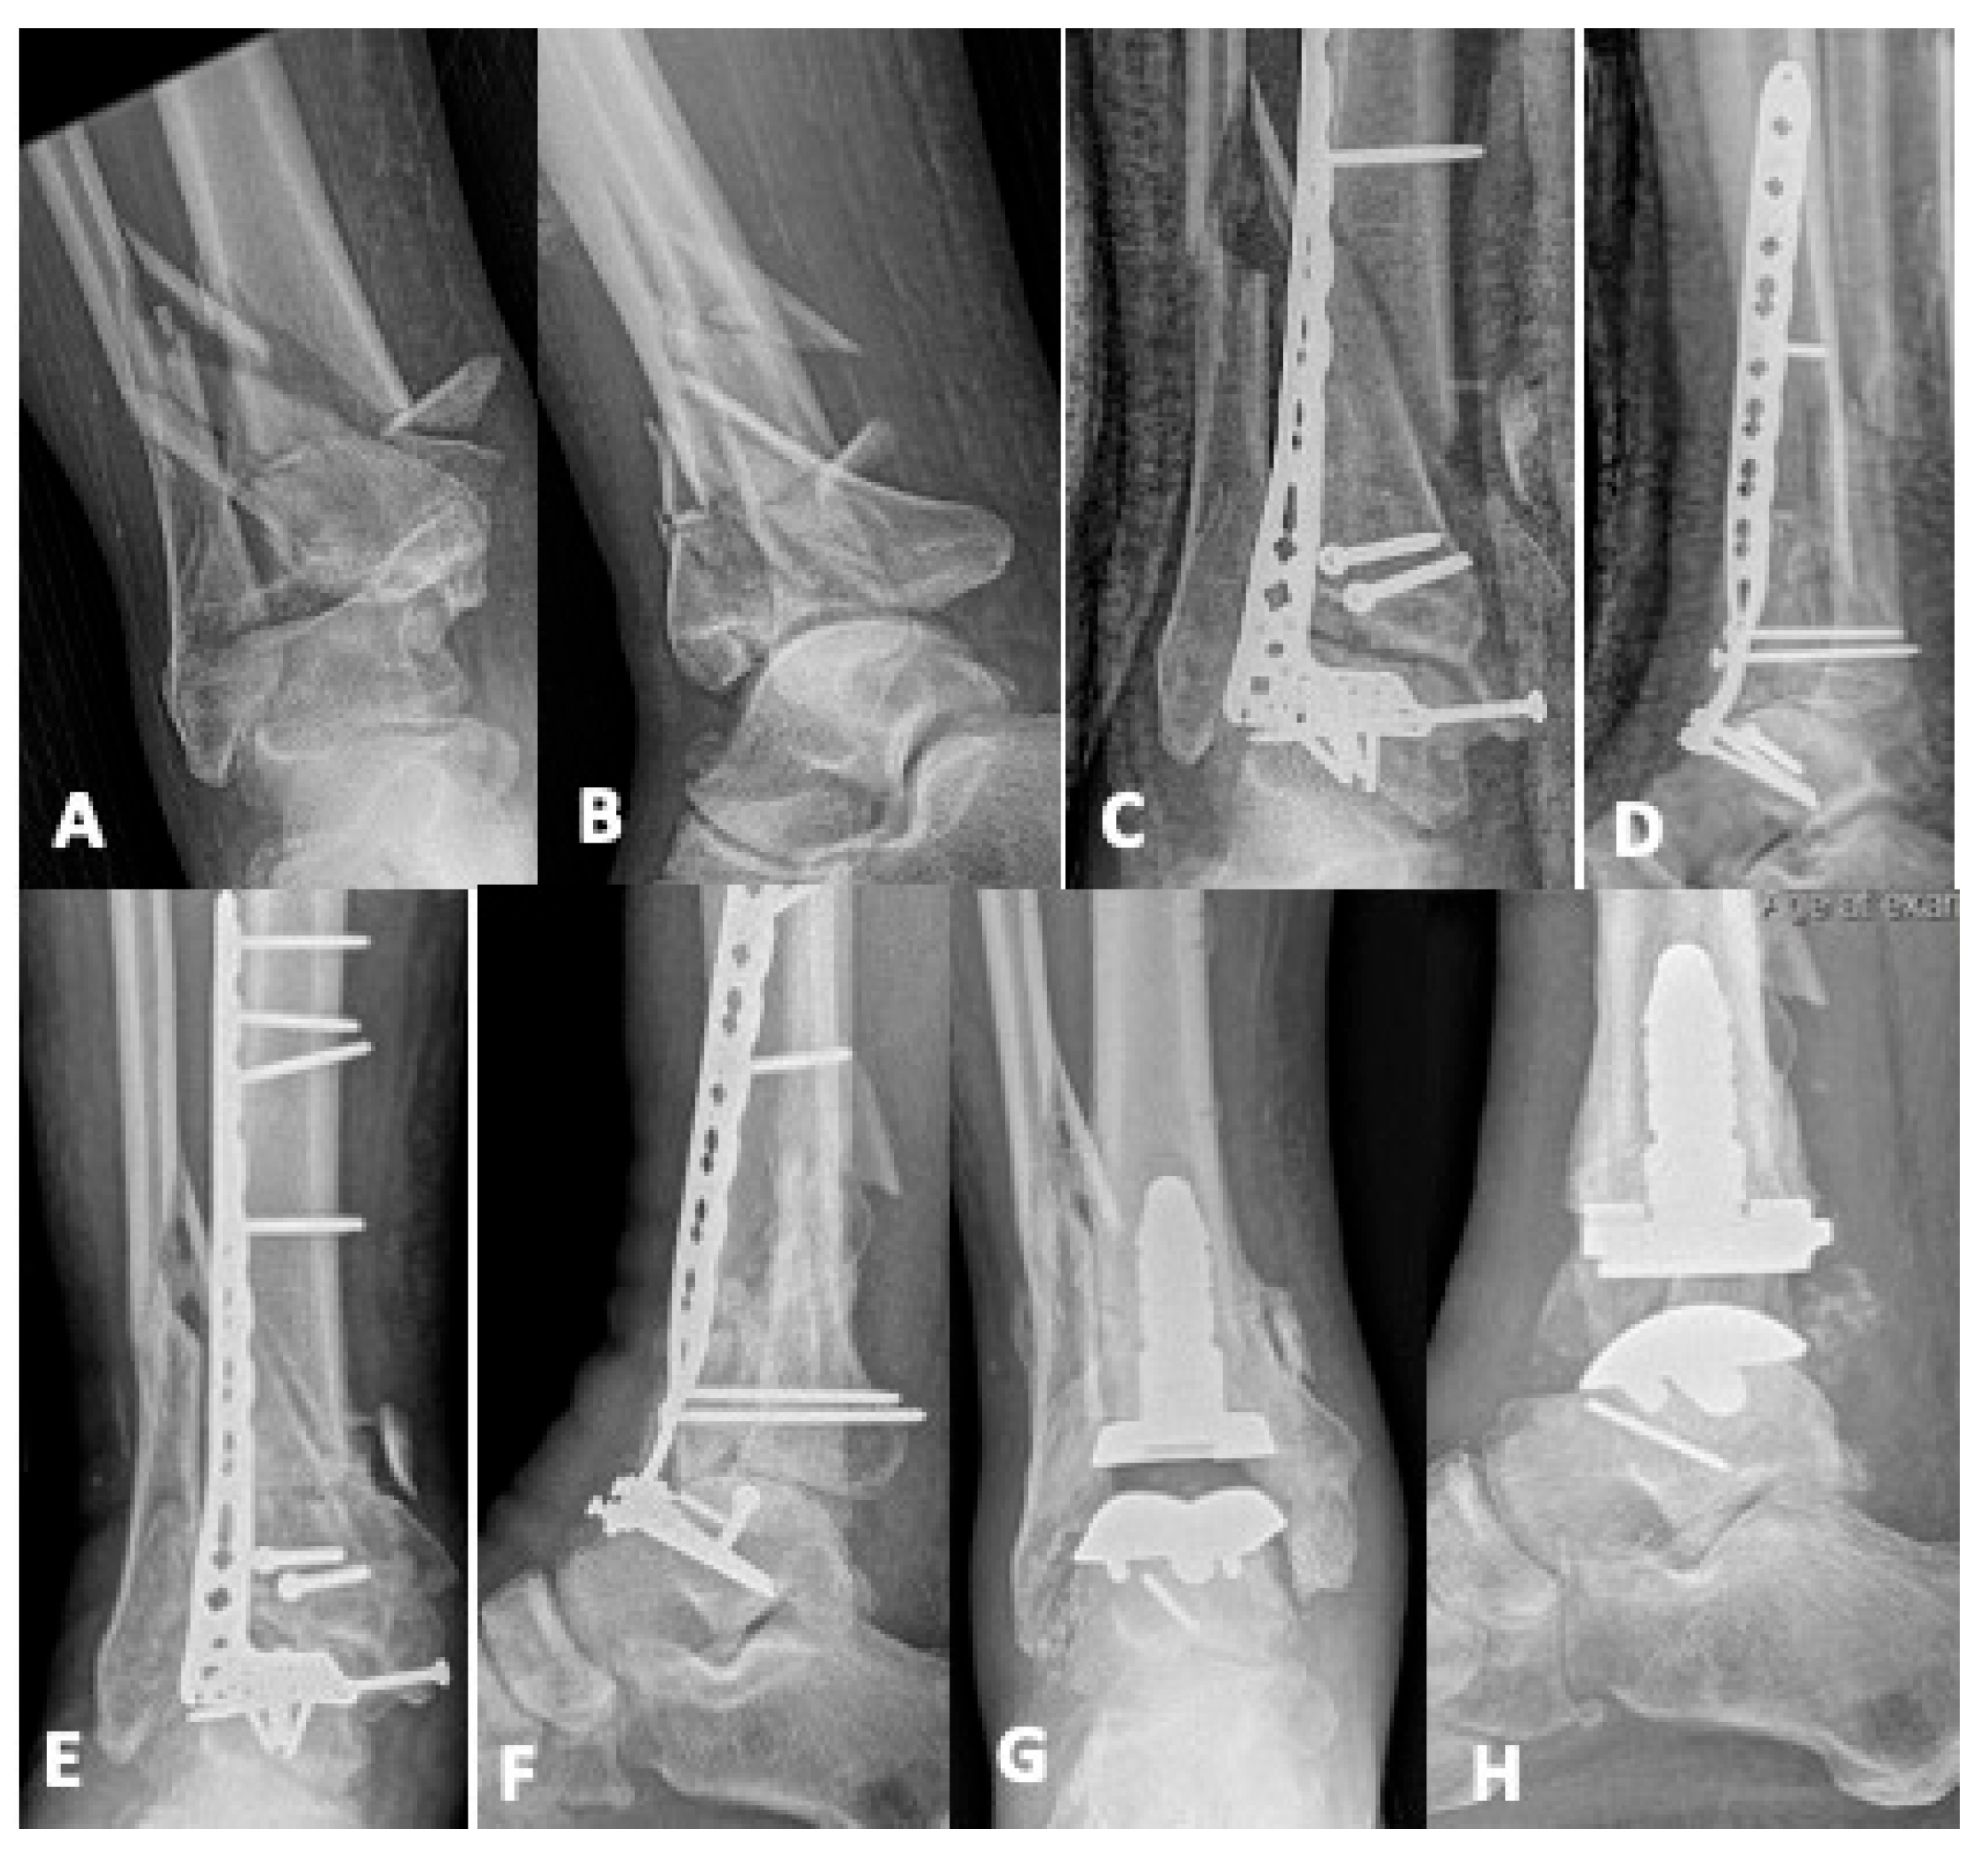

5.1. Revision Operative Fixation

5.2. Joint-Sacrificing Reconstruction

5.2.2. Tibiotalar Arthrodesis